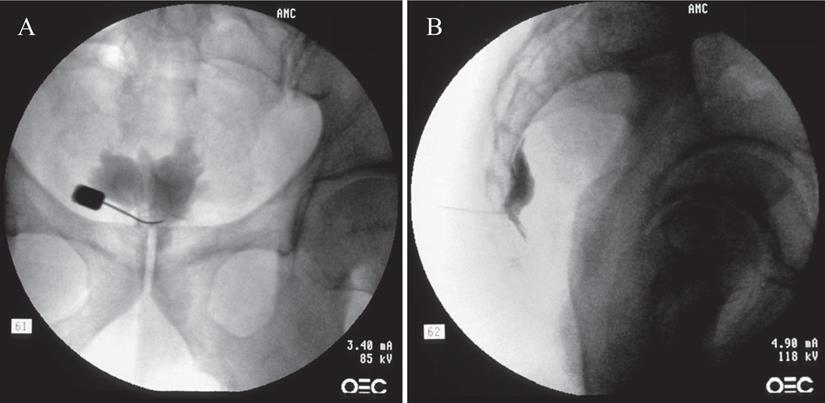

All procedures were performed on an outpatient basis. After informed and written consent, the procedure was performed using a transsacrococcygeal approach [15]. Medications or sedatives were not used before the procedure to prevent incidental neural damage and allow the patient's cooperation during the procedure. The patient was placed on the table in the prone position with a pillow under the lower abdomen. The intergluteal crease, anus, and surrounding area were prepared and draped in a sterile fashion. The procedure was performed under fluoroscopic guidance. After a true lateral image was obtained, skin and soft tissue were anesthetized with 1% lidocaine over the sacrococcygeal disc after identifying the disc in the lateral projection. A 25-G Quincke spinal needle (TaeChang Industrial Co., Ltd., Gonju-si, Chungcheongnam-do, Korea) was inserted under fluoroscopic guidance through the sacrococcygeal disc. The needle placement was confirmed by the injection of 0.2-0.5 mL of a contrast medium (Omnipaque; Nycomed Imaging, Oslo, Norway) (Fig. 1). After negative aspirate, 1-3 mL of local anesthetic (0.125-0.25% bupivacaine) was injected.

Figure 1

Fluoroscopic images of the ganglion impar block: transsacrococcygeal approach. (A) Anteroposterior view. The contrast flow in the midline at the upper coccyx. (B) Lateral view. The contrast flow just anterior to the upper coccyx showing comma sign.